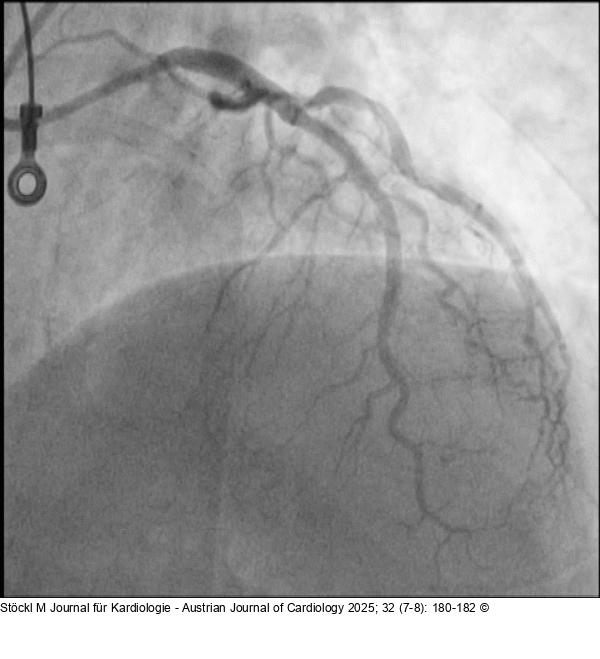

Abbildung 8: Ergebnis Ergebnis der Stentimplantation |